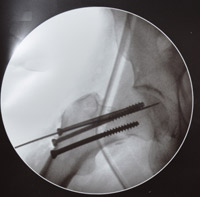

Выполнено 116 операций тотального эндопротезирования тазобедренных суставов.

На  2011г.  по  ВМП  запланировано около  200  операций по тотальному эндопротезированию  тазобедренного  сустава.